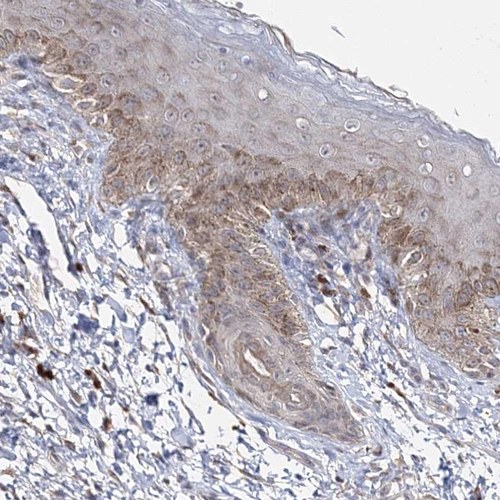

Immunohistochemical staining of human skin shows moderate cytoplasmic positivity in squamous epithelial cells.